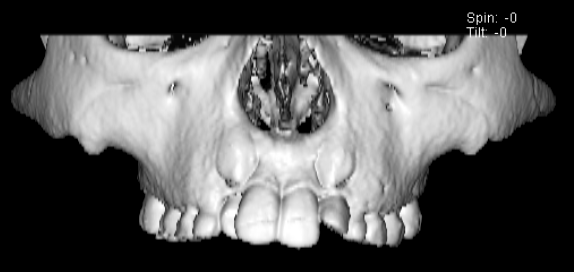

治療法:上顎急速拡大装置+クリアスナップ+フェイスマスク+上顎3番は開窓牽引CT写真にて位置確認

FX(フェイシャルアキシス)は85度なので東洋人の平均値に近く、下顎が前方に過剰成長するリスクは強くはありません。

しかしやはり上顎は劣成長で、下顎が優位な状態ではあります。

上下顎のギャップはありますが、顔面自体の幅径は良好な値を示していますので、スペース不足は拡大することによって解決できポテンシャルはあると考えられます。

左右の非対称もさほど強くありません。

骨年齢は実年齢よりも低めなので、今後下顎の旺盛な成長が見込まれます。

検査時のレントゲン分析では、上下顎の関係は、上顎の劣成長があり下顎前突傾向という値がでておりましたが、前歯ジャンプ後はフェイスマスクの効果もあり、上下顎の関係は正常化しています。

上顎が若干優位になっていますので、今後の下顎の成長のための貯金になっているくらいです。